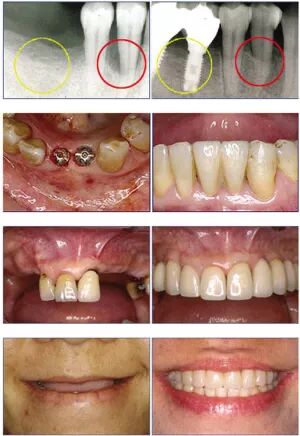

种植牙也叫人工种植牙,并不是真的种上自然牙齿。它是将与人体骨质兼容性高的生物材料(一般称作种植体)植入牙槽骨中,然后在种植体上做出假牙的一种修复方式。

种植牙以无需磨损邻牙、咀嚼功能强大、生命力更长久、自然逼真被称为人类的第三副牙齿,已经逐渐成为当今国际口腔医学界公认的缺牙首选修复方式。

普通人工种植牙的治疗及修复大致分为三个阶段:

(1)术前准备阶段。如拔掉残根、龋齿、治疗牙周病及去除不良假牙、调改和纠正不良咬合关系等。

(2)种植体植入手术阶段。您的医生根据术前设计方案,通过手术将种植体植入骨内。手术通常在局部麻醉下进行,手术时间约为10分钟到1小时。

(3)种植义齿修复阶段。术后三至六个月,安装恒久牙冠或义齿。进行取模、义齿制作、戴牙等工作。